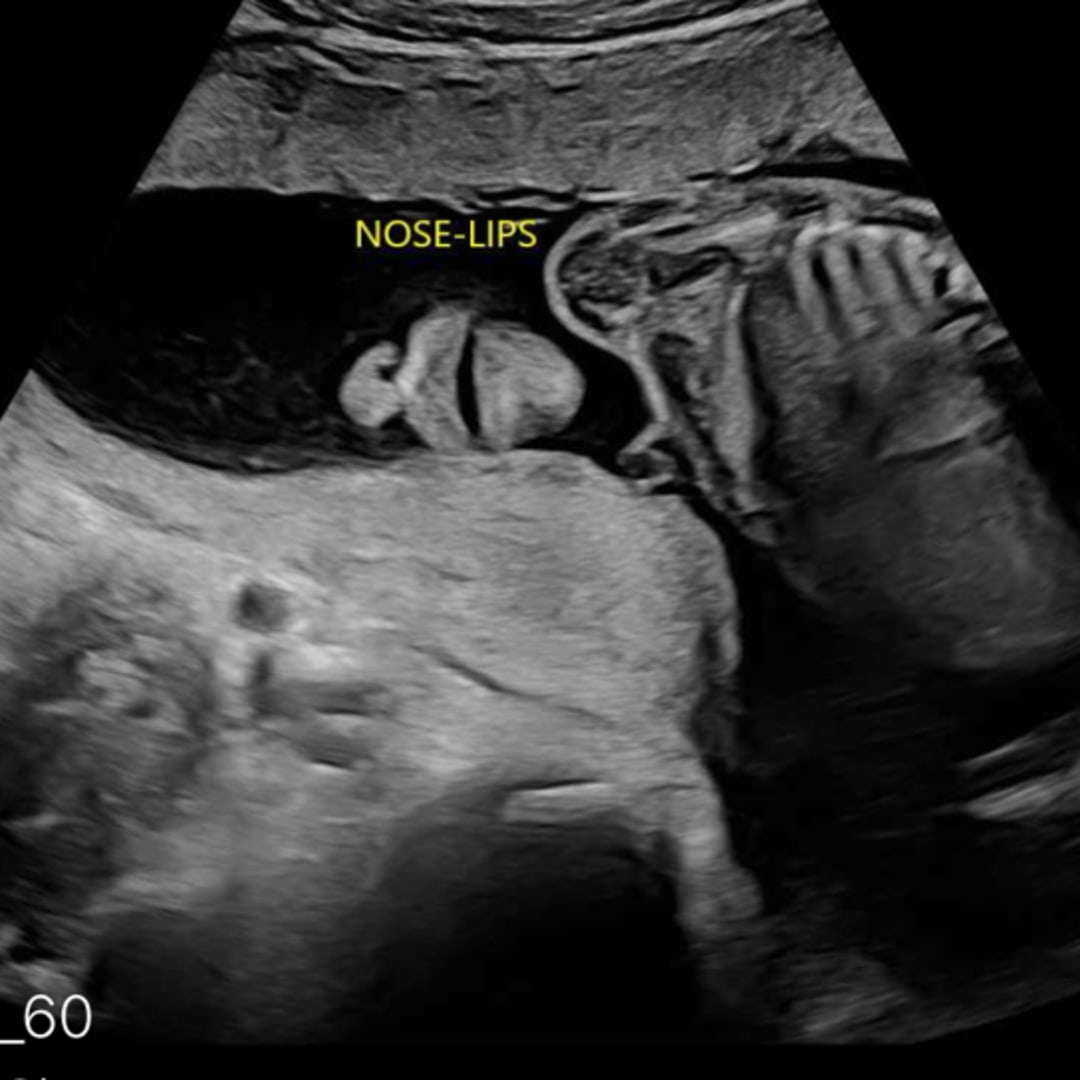

Greetings from little one